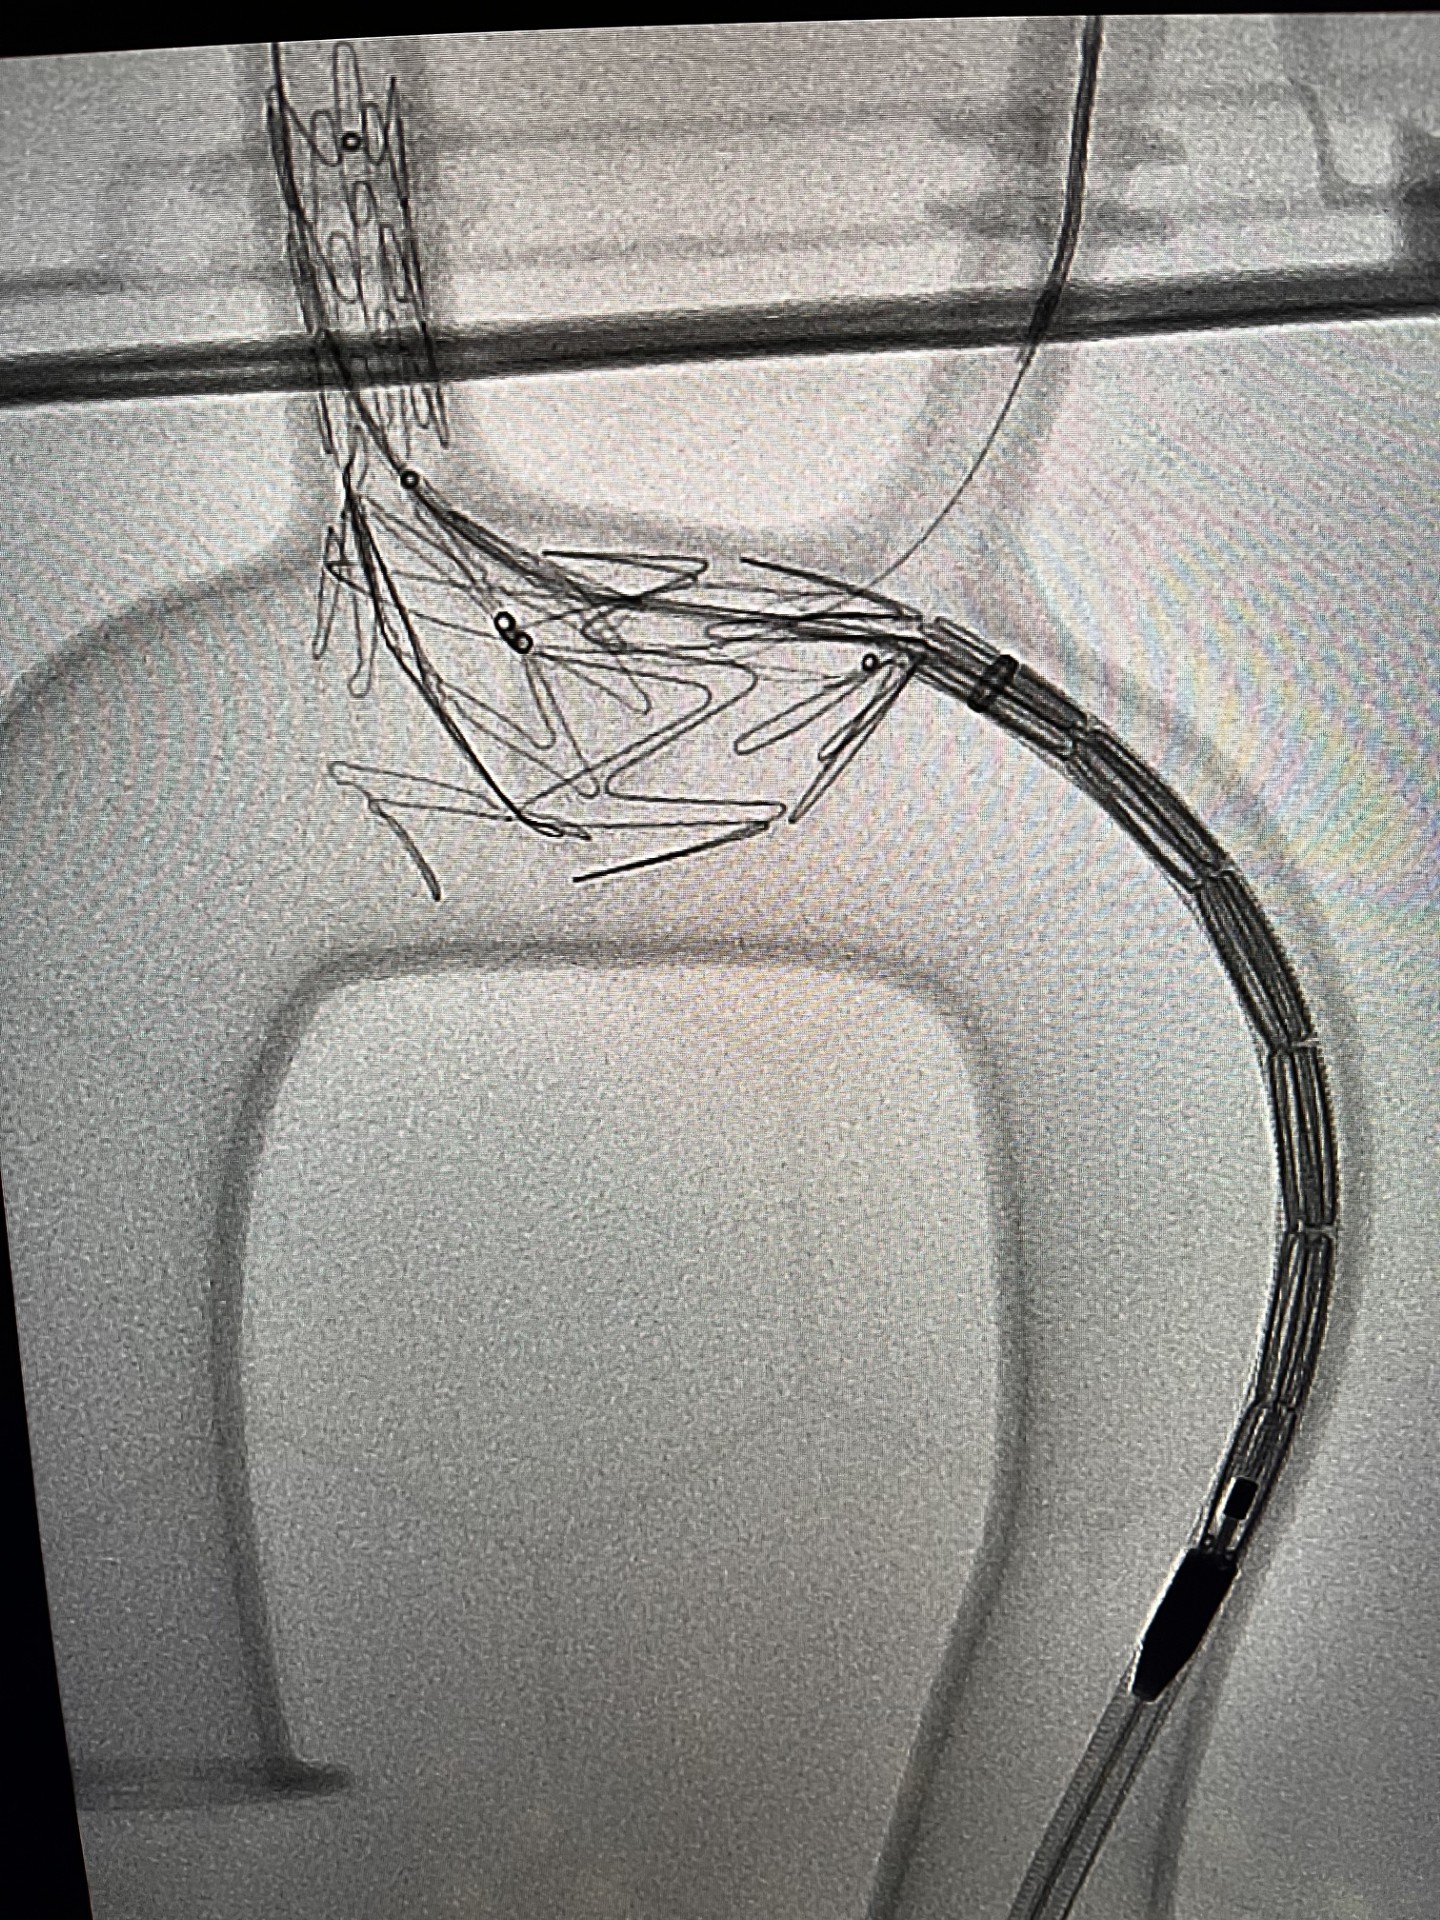

Pod koniec marca br. wykonano pierwszą w województwie pomorskim i trzecią w Polsce operację patologii łuku aorty systemem NEXUS TRE. Dzięki takiej procedurze udało się choremu uniknąć rozległej operacji kardiochirurgicznej z otwarciem klatki piersiowej oraz krążeniem pozaustrojowym.

Zespół chirurgów naczyniowych „Szpitali Pomorskich” rozpoczął w 2023 r. zabiegi endowaskularne w obrębie łuku aorty, dołączając tym samym do elitarnych oddziałów w Polsce. Obecnie ma na koncie liczne, wykonane z powodzeniem zabiegi.

Zabieg był dodatkowo wyjątkowy, gdyż chory obarczony jest niedrożnością obu tętnice szyjnych, odpowiedzialnych za dostarczanie krwi do mózgu. Czas zabiegu oraz zaangażowanie anestezjologa dr Pawła Dutki miał tu decydujące znaczenie — mówi doktor Ryszard Zając, ordynator Oddziału Chirurgii Naczyniowej Szpitala św. Wincentego a Paulo w Gdyni

Udaną operację przeprowadzono ze wsparciem specjalisty klinicznego, doktora Alana Abilio, który przyjechał z Brazylii. Chory bez powikłań udał się w piątej dobie do domu.